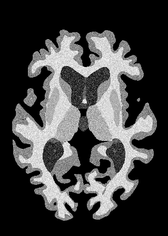

4.2 Registration to a 100 micron ex-vivo brain MRI volume

To showcase the efficacy of our method on real large scale images, we register a 250 in-vivo MRI image (Lüsebrink et al., 2017) to a 100 ex-vivo FLASH human brain volume (Edlow et al., 2019). This represents an inverse problem with more than 11.2B optimizable parameters (compared to 20M for clinical datasets), or 44.8GB of GPU memory. The entire problem does not fit on most GPUs, necessitating distributed multimodal registration. We optimize a composite transform - affine followed by a diffeomorphic mapping; details can be found in Section E.1. Multimodal deformable registration took 58 seconds on 8 NVIDIA A6000 GPUs, which is unprecedented at this resolution. Fig. 6 shows qualitative results, highlighting the ability to register highly detailed structures such as cerebellar white matter; these structures are not visible at macroscopic scales. The resultant advantages of performing registration at this scale can allow researchers to characterize the neuroanatomy at microscopic resolutions and allow morphometric analysis of cortical layers and subcortical nuclei among other structures.